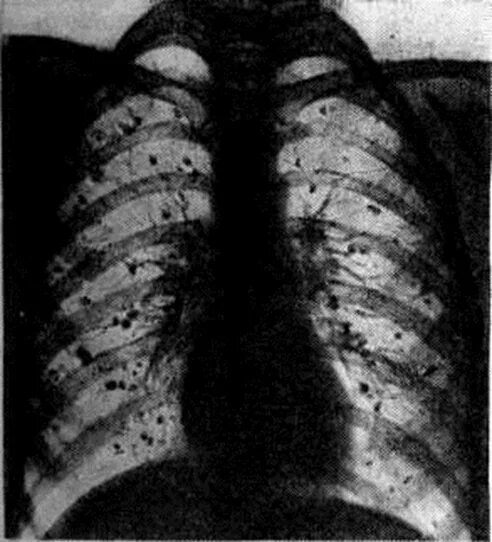

Гистоплазмоз это